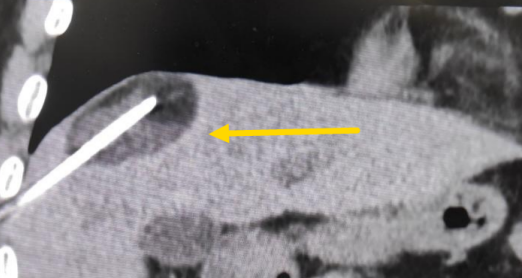

這個患者病變位置刁鉆,穿刺難度大,冷凍消融的難點在于既要不損傷膈肌和肺組織,同時又要盡最大可能完全消融腫瘤。術前陳寶瑩主任、李鐵柱教授、兀云飛醫生詳細設計進針路徑、布針計劃,術中微創團隊協調配合,李鐵柱教授仔細操作,精準到位,順利完成兩個病變的布針,遂啟動治療,先快速降溫到-150多度,再升溫至15?,經過兩個循環反復,即刻觀察到病變完全被冰球覆蓋,同時周圍臟器無損傷,術中患者幾乎沒有疼痛,還和醫生聊起了天。

術中冰球形成